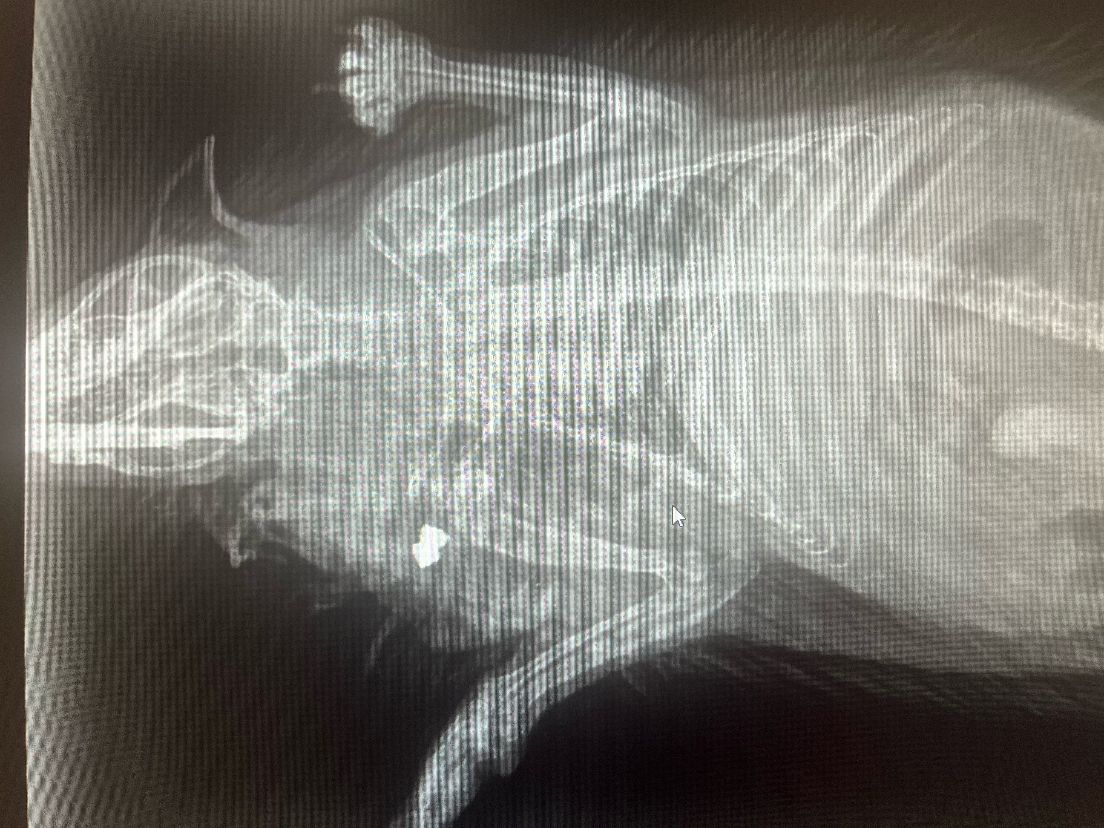

She said: “Following initial treatment, I soon realised that something was seriously wrong so on Monday 25 March I took him to the vets. It was then discovered that the hedgehog had been shot.”

The vet believed it may have occurred around a week before and suspected it could have been a deliberate attack.

“The pellet missed his head and caught the shoulder,” said Ginny, “There was no bone injury but the impact had dislocated his shoulder.”

(Image: RSPCA / Pembrokeshire Hogspital)